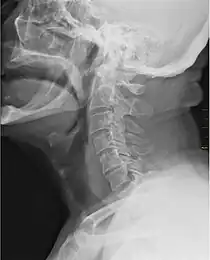

![]() X-ray showing the throat, seen as a dark band to the front of the spine | |

In vertebrate anatomy, the throat is the front part of the neck, internally positioned in front of the vertebrae. It contains the pharynx and larynx. An important section of it is the epiglottis, separating the esophagus from the trachea (windpipe), preventing food and drinks being inhaled into the lungs. The throat contains various blood vessels, pharyngeal muscles, the nasopharyngeal tonsil, the tonsils, the palatine uvula, the trachea, the esophagus, and the vocal cords.[1][2] Mammal throats consist of two bones, the hyoid bone and the clavicle. The "throat" is sometimes thought to be synonymous for the fauces.[3]